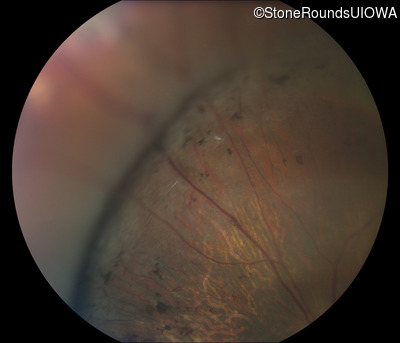

Fundus Photography - Right - 10/200

Exemplar